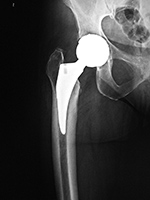

Revision total hip prosthesis |

Triflange acetabular component total hip revision arthroplasty with long femoral stem |

Triflange acetabular component total hip revision arthroplasty |

The revision prosthesis was placed because of an earlier periprosthetic fracture. There are two cable wires proximally and two cerclage wires distally. |

|

83 year-old woman |